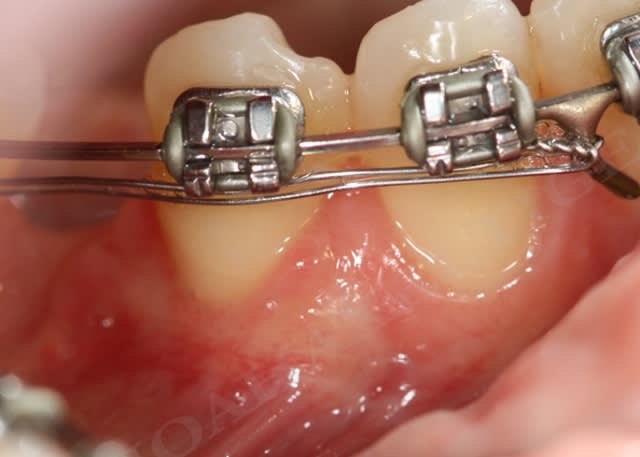

En ce qui concerne la mobilité dentaire, c'est une notion que j'ai appris par le biais du cas suivant :

la patiente présente des rétractions gingivales au niveau du bloc incisivo canin inférieur suite à un traitement parodontal initial. Le problème paro de la patiente est sous contrôle et la patiente désire améliorer l'environnement gingival de 33 à 43.

Très bien madame, on y va :

Greffon conjonctif nhbbmi - Eugenol

Lambeau mucogingival y1a6cr - Eugenol

Initial roeu0t - Eugenol